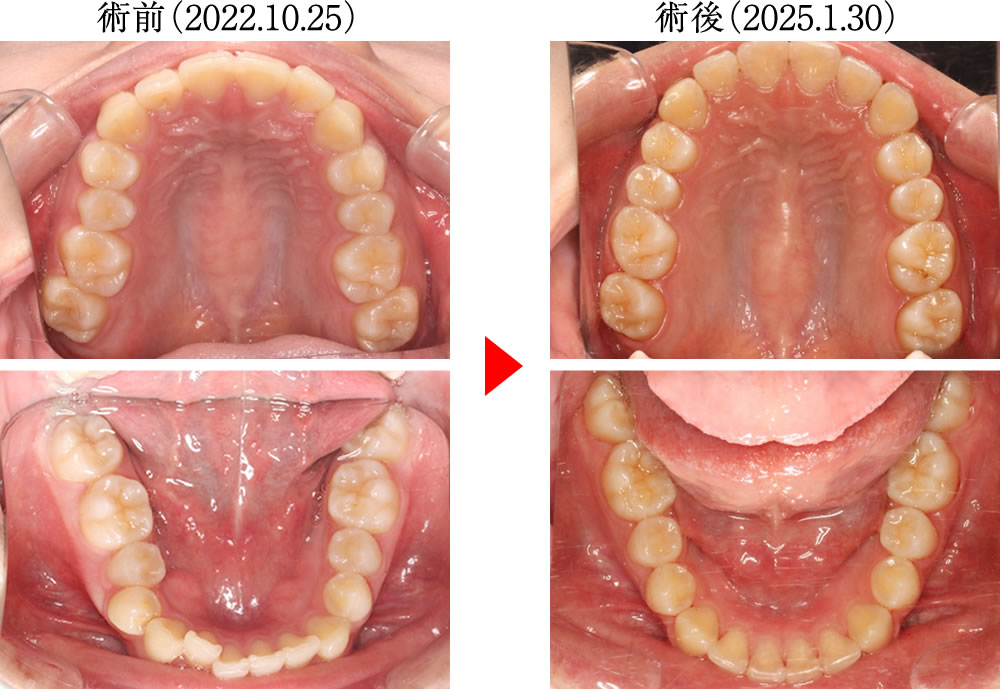

術前は歯が重なり合うように乱れた歯並びでしたが、術後は歯が理想的に整列し、きれいで大きなアーチを形成する歯並びへと改善しました。